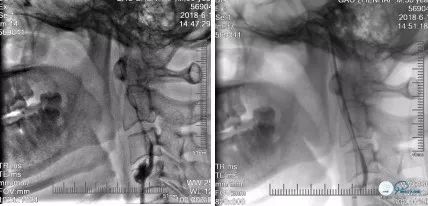

Pilot 50微导丝(190cm 0.014″)携Echelon 10微导管多次尝试通过左颈内C1闭塞段,但未成功,遂撤出。经8F球囊导管送入普通加长泥鳅导丝(260cm 0.035″)沿加硬泥鳅导丝路径小心通过左颈内C1闭塞段至C4远端,撤出加硬泥鳅,并沿普通加长泥鳅导丝送入多功能导管至C2末段(图11)

再次沿多功能送入Pilot 50微导丝(190cm 0.014″)携Echelon 10微导管,导丝头端置于左侧大脑中动脉M1远端,跟近Echelon 10微导管,微导头端置于左侧大脑中动脉M1远端,撤出Pilot 50微导丝,微导管内造影可见左侧大脑中动脉M2以远显影,证实微导管在真腔内(图12)

沿微导管送入Transend微导丝(300cm 0.014″),头端至左侧大脑中动脉M1远端,撤出微导管及多功能导管,沿Transend微导丝送入Ultra-soft球囊(2.0mm*20mm)至左颈内动脉C5段,沿左颈内动脉C5-C1段由远及近重叠扩张局部血管(图13)

撤出Ultra-soft球囊,经8F球囊Guiding导管于左颈C1段近端手推造影提示左颈内动脉管腔不光滑,前向血流较前改善(TICI分级2a级)(图14),并观察5分钟后再次造影提示管腔无明显回缩。